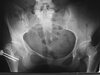

SCFE: demographics, Risk factors

• Obese, Males, African Americans, during puberty/growth spurt 10-14ish range

• Bilateral 17-50% avg 25%

• # 1 risk factor: obesity > #2 acetabular retroversion/femoral anteverision> hx of radiation